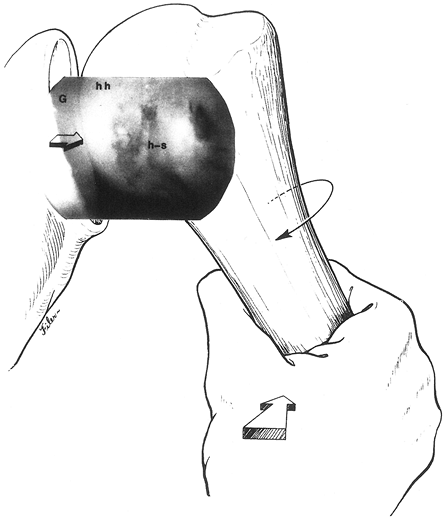

Similarly, large Hill–Sachs or reverse Hill–Sachs lesions,

posterolateral or anterolateral humeral head impaction fractures

respectively, can affect this articular relationship (Fig. 80.2) (22,131,133,134).

These fractures are created by direct contact between the humeral head

and the glenoid rim during shoulder dislocations. While these lesions

are present in more than 80% of anterior dislocations and 25% of

anterior subluxations, they are rarely a contributing factor to

instability. They become biomechanically relevant to joint stability

when osteoarticular loss involves greater than 30% of the humeral head

surface.

![]() |

|

Figure 80.2. Axial MRI with contrast demonstrates anterior capsular stripping (large curved arrows) with an associated Bankart lesion. In addition, a large Hill–Sachs lesion can be seen posteriorly (smaller straight arrows).